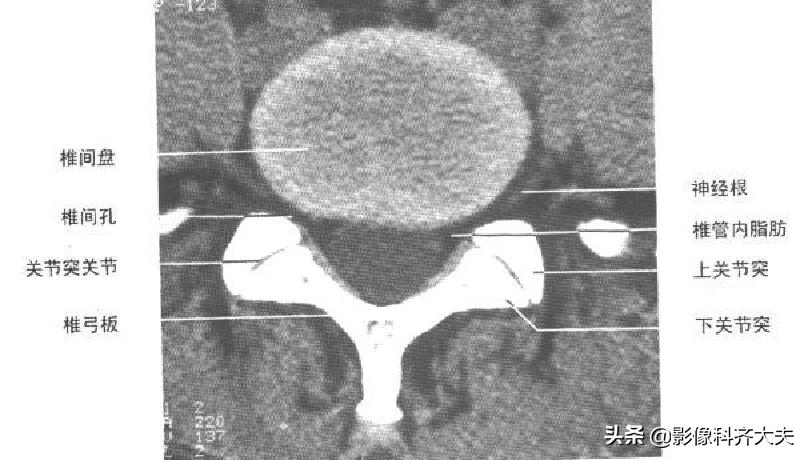

CT及MRI表现:

①正常腰椎间盘后缘不超过椎体骨性终板的后缘,且中部略有凹陷呈肾形。椎间盘脱出表现为局部突出于椎体后缘的弧形软组织影,通常与椎间盘相连,且密度多一致,并可见硬脊膜外游离髓核。髓核在椎间盘平面上方或下方,其密度低于椎骨但高于硬脊膜及椎旁软组织,突出的椎间盘可钙化。

②硬脊膜外脂肪受压、移位,甚至消失,硬脊膜下腔前缘或侧方受压变形。

③向侧后方突出的椎间盘,可使侧隐窝前、后径缩短,压迫相应的脊神经根使其向后移位;脊神经根亦可因水肿而增粗。

椎间盘膨出CT及MRI表现:

①轻度膨出时表现为椎间盘后缘正常肾形凹陷消失,圆隆饱满。

②重度时弥漫膨出的间盘边缘明显向四周均匀一致增宽,超出上下椎体边缘,但椎间盘仍然对称,没有局部突出,外形保持椭圆形,可伴真空变性。严重时可造成硬膜囊受压狭窄,马尾神经受压。